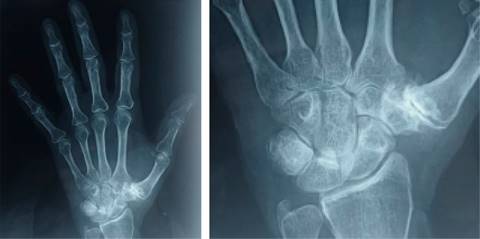

La artrosis trapecio-metacarpiana o rizartrosis es una patología que produce dolor, disminución de la fuerza y pérdida de destreza en la movilidad del pulgar, limitando la función global de la mano. Afecta a 20% de la población mayor de 50 años, principalmente en la mujer; provoca desgaste crónico y progresivo del cartílago que, en la mayoría de los casos, ocurre en ambas manos. Son típicos los episodios de dolor intenso en la base del pulgar que aumentan al movimiento y al realizar esfuerzos con la mano. Los movimientos del pulgar se reducen, lo que ocasiona rigidez progresiva. En los casos avanzados, se aprecia deformación por inestabilidad, subluxación y formación de osteofitos (Figura 1). La radiografía simple permite corroborar el diagnóstico utilizando la clasificación por estadios de Eaton y Littler (Tabla 1). Cuando el tratamiento médico conservador resulta ineficaz, se recurre a la cirugía. La finalidad de la prótesis trapecio-metacarpiana es eliminar el dolor y restaurar la longitud del pulgar, la fuerza y funcionalidad (Figura 2). El procedimiento quirúrgico por lo general se realiza de forma ambulatoria, consiste en eliminar la porción del hueso que está desgastada y reemplazarla con la prótesis, la recuperación es rápida y en dos o tres semanas se inicia la rehabilitación.

Figura 1: Radiografía anteroposterior simple de mano derecha que muestra rizartrosis en estadio III de Eaton y Littler, caracterizada por disminución del espacio articular, esclerosis, osteofitos mayores de 2 mm y subluxación articular trapecio-metacarpiana que no mejoró con tratamiento conservador.